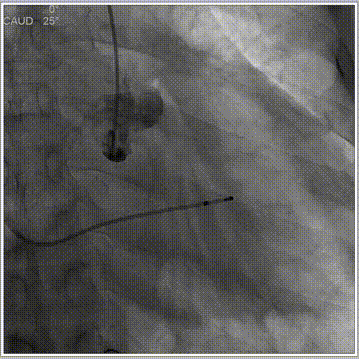

主动脉根部造影

球囊预扩

释放工作位评估

术后造影评估

人工瓣膜精准定位